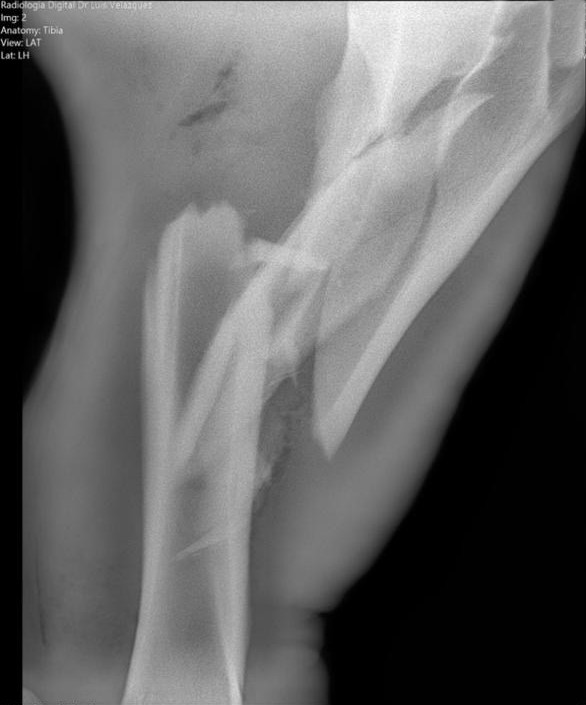

Radiología Digital como Herramienta Complementaria en el Dictamen de Bienes Muebles

Desde el descubrimiento de los rayos “X” y las placas radiográficas por Wilhelm Conrad Roentgen y su posterior difusión a través de la Asociación Físico médica de Wurzburg el 28 de diciembre de 1895, que fue la primera asociación que habló de los nuevos rayos que podían penetrar el cuerpo y fotografiar los huesos, ha habido muchos cambios tanto en la forma de obtener, procesar e incluso en la forma de visualizar, manejar y almacenar las placas radiográficas.